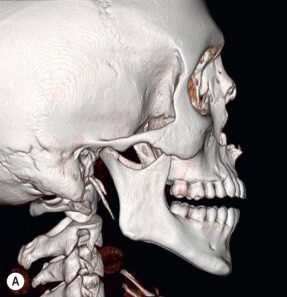

Presently, the treatment of injuries is organized both by severity and anatomic area to permit the smallest exposure possible to achieve a good result [computerized tomographic (CT)–based facial fracture treatment].